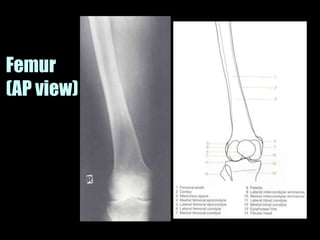

This document provides an overview of normal musculoskeletal imaging. It discusses basic x-ray concepts and densities. It then reviews normal anatomy as seen on x-rays of the skull, spine, pelvis, chest, and extremities. Key anatomical structures are labeled on example x-rays for the shoulder, hip, knee, and foot. Quizzes are included to test recognition of anatomical structures and patient age based on x-rays.